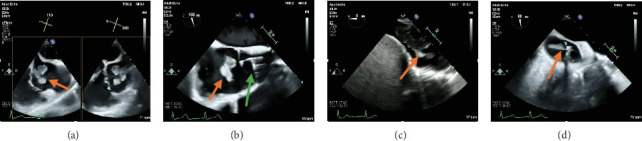

AngioVac机械抽吸系统已在文献中出现,作为一种可行的治疗选择,用于心脏手术高风险的心内肿块和血栓患者。值得注意的是,它已被证明是一种有效的治疗方式,为减少血栓在恶性肿瘤的设置。我们报告一例在晚期恶性肿瘤合并粪肠球菌心内膜炎的情况下,右心房大血栓从肝静脉延伸的重复血管血管消肿。

The AngioVac mechanical aspiration system has emerged in the literature as a viable treatment option for patients with intracardiac masses and thrombi and who are deemed high risk for cardiac surgery. Notably, it has been shown to be an effective treatment modality for the debulking of thrombi in the setting of malignancy. We present a case of repeat AngioVac debulking of a large right atrial thrombus with extension from the hepatic vein in the setting of advanced malignancy complicated by Enterococcus faecium endocarditis.